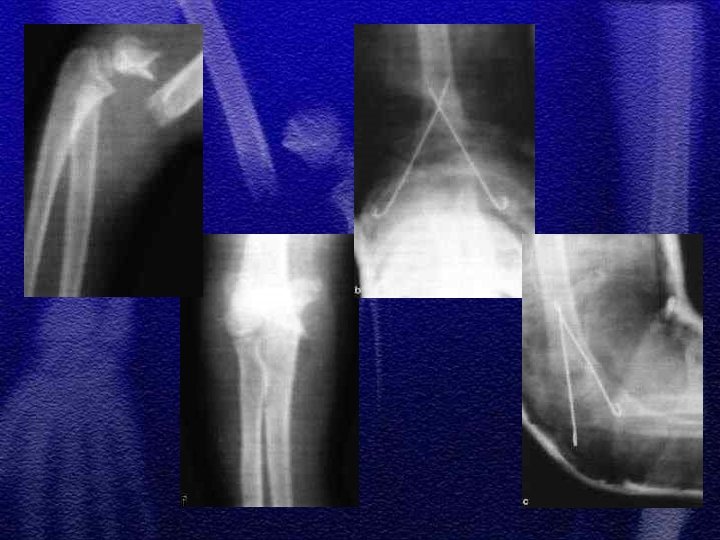

1. Szczyt występowania złamania 3 -10 rok życia, co wynika z budowy anatomicznej, która predysponuje do ww. złamań 2. Wiotkość torebki stawowej i więzadeł usposabia do przeprostu 3. Linia złamania przebiega w przynasadzie w miejscu jej ścieńczenia (dół dla wyrostka dziobiastego oraz wyrostka łokciowego )

§ Wyprostne - 95% § Zgięciowe - 5% § Klasyfikacja wg Gartlanda

§ Repozycja zamknięta , unieruchomienie gipsowe § Repozycja zamknięta i zespolenie przezskórne dwoma drutami Kirschnera § Repozycja otwarta i zespolenie dwoma drutami Kirschnera skrzyżowanymi lub równoległymi § Wyciąg szkieletowy typu „Zeno”

§ Złamania otwarte § Złamania powikłane uszkodzeniem naczyń i nerwów § Niemożność utrzymania poprawnego ustawienia odłamów